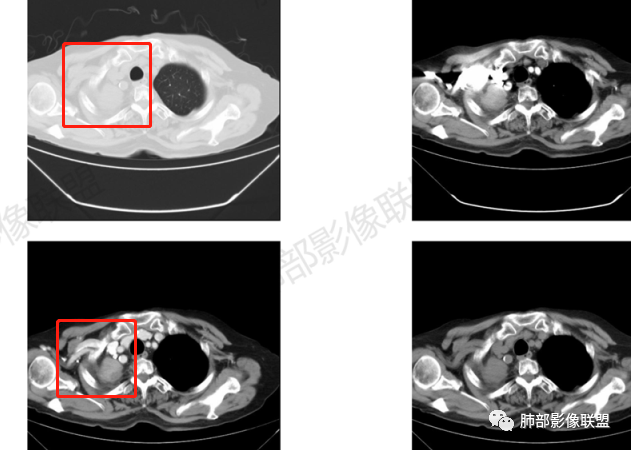

支气管影

前,后段都在,没有堵塞

支气管壁增厚,周围磨玻璃边界不清,提示炎症。胸膜下钙化符合结核

结核是肯定有。现在最大问题是尖段

近端显示不清,但是远端是粘液栓,可以认为是还行的

如果是近端鳞癌,远端应该会堵塞,不会整个肿块里面还有较为通畅的支气管

这个区域我们看到密度与周围一致,并不是肺癌伴周围不张的感觉,所以鳞癌暂时是不支持的

相应上叶尖端及前段支气管开口未能追踪(阻塞),开口处见钙化。病灶渐进性强化,并衬托出较完整尖段及前段含液支气管影。支气管开口区域未见异常高密度强化(如类癌等)及相对乏血供区(如鳞癌)。病灶区未见液化坏死。右上纵隔及胸廓入口区未见病灶胸膜外突破(栽赃)。